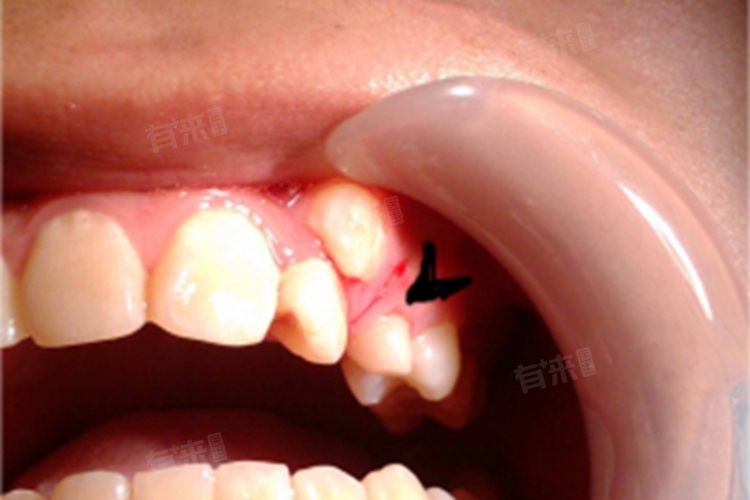

2、多生牙:多生牙是指超出正常数量的额外牙齿,可能会阻碍恒牙的正常萌出路径,甚至引起拥挤或错位。其成因复杂,可能与遗传相关。一旦确诊,通常建议手术移除多生牙,避免对其他牙齿造成影响。手术后需密切关注伤口愈合情况,并根据医生建议进行后续治疗或调整。

此外,牙龈上的新牙齿也可能与囊肿或其他病理状态有关,这些病变会干扰恒牙的正常萌出。这类问题通常需要影像学检查(如X光)来诊断。治疗手段依据具体情况而定,可能涉及手术切除囊肿以及后续的牙齿矫正计划。